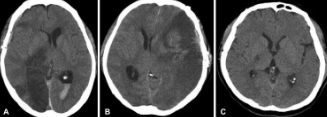

- 컴퓨터 단층 촬영(CT) 스캔: 뇌출혈 여부를 빠르게 확인하고, 뇌경색의 위치와 크기를 파악합니다.

- 자기 공명 영상(MRI): 더 정밀하게 뇌 구조를 확인하여 뇌경색의 유형과 위치를 결정하는 데 사용됩니다.